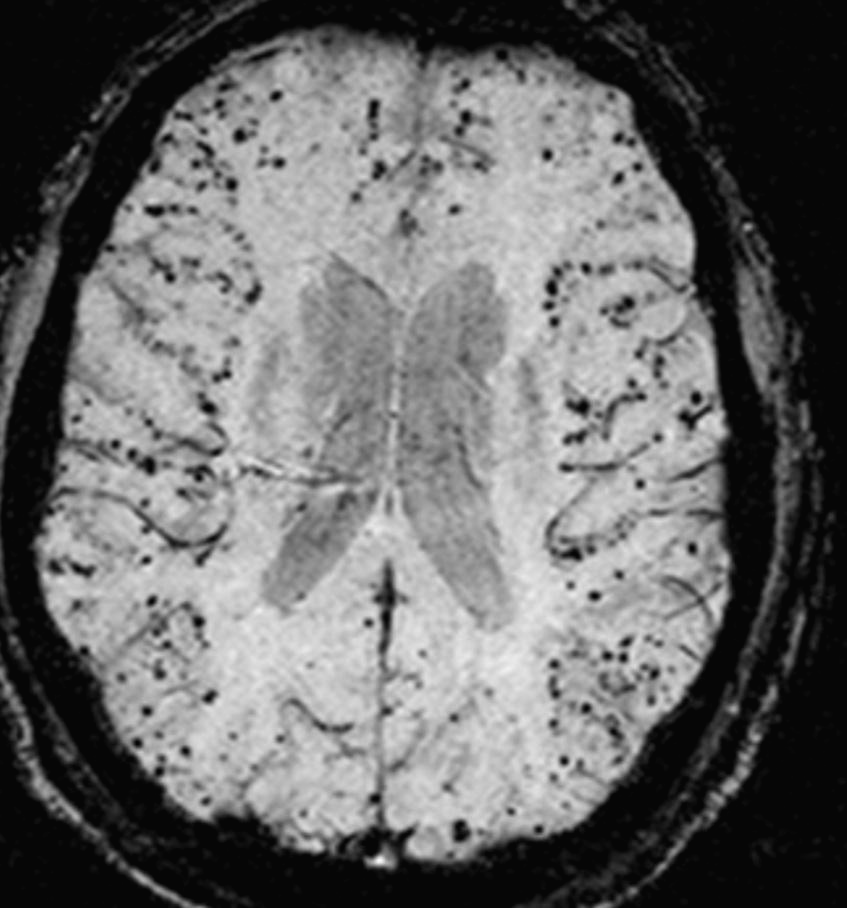

2. 베타 아밀로이드 단백질

임현국 여의도성모병원과 강동우 서울성모벼원 정신건강의학과 교수팀은 2010~2016년까지 가톨릭중앙의료원 산하 병원의 치매 관련 뇌 영상 데치터베이스에 저장된 영상을 분석한 결과 '베타 아밀로이드 단백질'이 뇌에 축적하면 치매 발병 가능성이 커졌다고 밝혔습니다.

연구진에 따르면 베타 아밀로이드 단백질은 알츠하이머 치매의 주된 원인 물질로 인지기능 저하가 나타나기 10~15년 전부터 쌓이게 된다고 합니다.

연구진은 뇌 영역 촬영 영상을 비교해보니 특정 부위의 뇌 신경 활성도가 떨어졌고, 인지장애 발생 예측률이 90% 이상인 것으로 나타났다고 합니다.

임현국 교수는 '생활하는 데 불편함을 느끼지 못하는 노인도 치매가 진행되고 있을 수 있다'며 '베타 아밀로이드 단백질 축적 여부를 관찰하면 본격적인 치매 증상이 나타나기 전에 치매 발병 가능성을 예측해 예방적 조치를 할 수 있을 것으로 기대한다'고 발혔습니다.